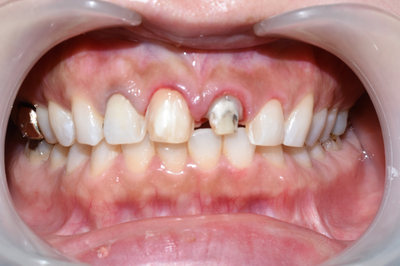

아래 사진은 이번에 치료하기 전 사진입니다.

![[시청역/광화문]라미네이트케이스:"치아가 작아서 옹졸해 보여요. 치아가 길어보이면 좋겠어요" 관련 이미지 1](https://pub-9f2bb3498faf4d1d8714b41df24753e3.r2.dev/content/clinics/archive/rseeanjxfu/naver_blog/yonseiyegam/assets/by_hash/0234b93ff367992c8cc665cab2b50ccfe0aa6f57b1f491fc490758a6cb211952.jpg)

대문이 중 하나는 라미네이트, 하나는 신경치료 후 크라운이 되어있는 상태였습니다.